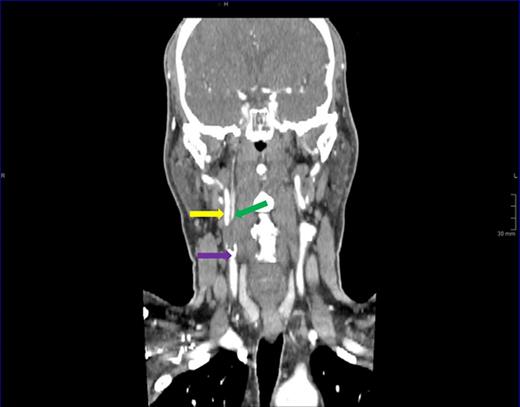

We report a very rare case of an extracranial ICA branch preventing complete occlusion of the ICA distal to a heavily atherosclerotic occluded proximal segment. A normal ICA distal to the occluded segment raised the suspicion that some blood flow was maintained. Surgical exploration demonstrated an aberrant ICA branch ∼2.5 cm from the bifurcation. Carotid endarterectomy was successful and this prevented further transient ischaemic attacks and potentially devastating stroke. Pre-operative CT carotid angiography was reviewed retrospectively and this aberrant ICA branch was identified, albeit with a faintly visible origin (Fig. 1).

Sagittal plane view of the right carotid artery. Carotid bulb (purple arrow) gives rise to the internal carotid artery (yellow arrow) and an aberrant distal branch (green arrow).